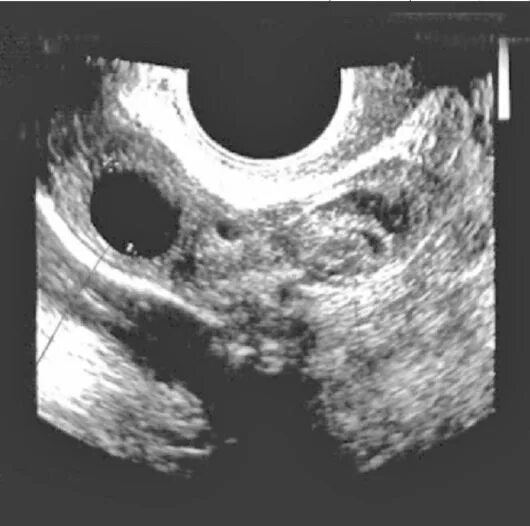

Перекрут придатков матки